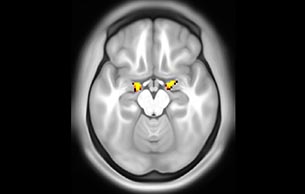

Advancing diffusion MRI

These images are produced using the ABCD protocol and illustrate the use of more sophisticated and accurate models of diffusion. The color FA maps are shown for reference. The diffusion tensor model represents the diffusion within each voxel as an ellipsoid.

Alternative models, such as constrained spherical deconvolution, better capture the rich information available with the use of high b-value dMRI and many sampling directions. In much of the brain, voxels contain multiple white matter tracts, and it is essential to capture this information to be able to perform accurate tractography and generate diffusion connectomes.

Diffusion acquisition on Achieva 3.0T dStream with matrix 140x141, 81 slices, FOV 240x240 mm, voxels 1.7x1.7x1.7 mm, TR 5300 ms, TE 89 ms, flip angle 78, MultiBand SENSE factor 3, partial Fourier 0.645, 102 diffusion directions, b-values 0 (6), 500 (6), 1000 (15), 2000 (15), 3000 (60) , scan time 2x 4:37 min. Images provided by Dr. Watts.